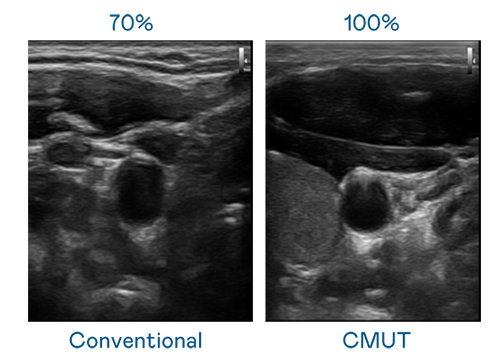

CMUT 技術是一種用電容式微機電元件來產生超音波訊號的技術。與傳統 PZT 壓電式技術相比,CMUT 頻寬增加 30%,更寬頻的超音波訊號讓影像解析度大幅提升,是實現高影像品質醫療超音波掃描、促進精準醫療發展的關鍵技術。

超音波影像的解析度高低,首先取決於探頭能發出的訊號頻寬。创世大发 CMUT 可提供高清晰的超音波訊號,提供高頻寬、高靈敏度、影像紋理細節更高的超音波影像,協助醫護人員縮短影像判讀時間及利用精準的醫療影像進行診斷。